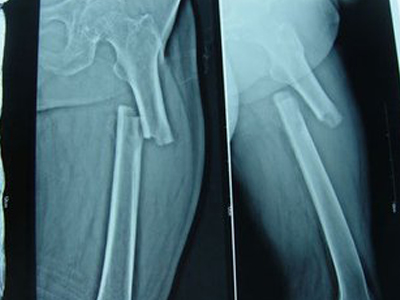

骨膜反应图 (51)

骨膜反应图 (50)

骨膜反应图 (5)